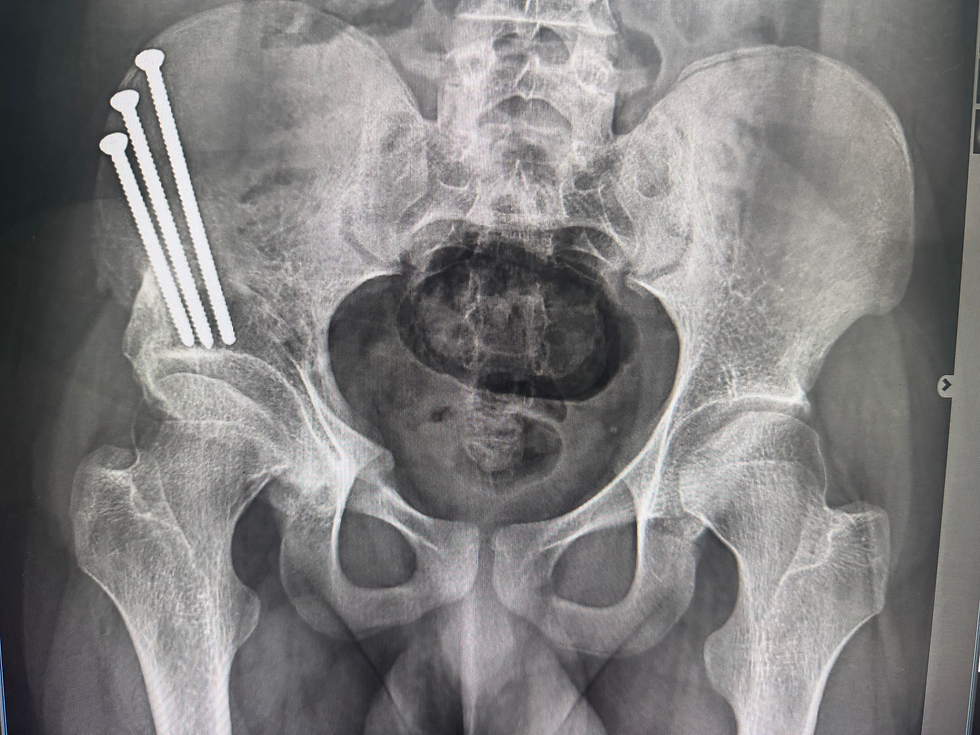

Radiografías (X-rays): miden la cobertura y alineación del acetábulo.

Osteotomía Periacetabular (PAO)

El procedimiento de referencia para la displasia de cadera en adultos. La cirugía reposiciona el acetábulo para que cubra mejor la cabeza femoral.

Mejora la estabilidad articular.

Protege el cartílago y el labrum.

Puede retrasar o prevenir la artritis.

Ideal en pacientes jóvenes con superficies articulares preservadas.